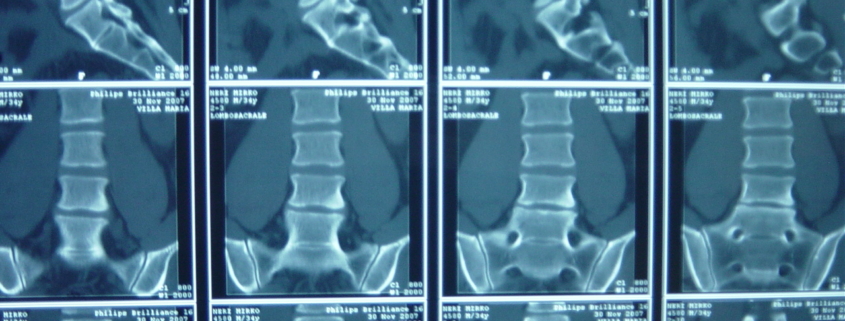

Lastra alla schiena. È bene rammentare che con la radiografia della colonna lombosacrale non si possono fare diagnosi di ernia del disco, ma solo escludere altre malattie con sintomi simili (tumori, forme infiammatorie, fratture, malformazioni ecc) La TAC e la RM sono pressoché sovrapponibili in termini di valore diagnostico per il medico;. Devo fare la lastra alla schiena!?. Ormai la schiena e il sedere mi fanno abbastanza male e ho solo 17 anni Grazie a tutti.

L’esame radiografico della colonna vertebrale completa (in toto) è un esame radiologico condotto mediante l’utilizzo di raggi X che riescono ad attraversare il corpo umano e a imprimersi in modo fotograficoIl risultato è un’immagine che evidenzia in modo differente ossa e scheletro rispetto ai tessuti molli (muscoli e pelle. Ho un problema alla schiena,una ernia L4L5 e responsabile di compressione sull’emergenza radicolare di L5 bilaterale Mi hanno mandato a fare un po’ di ciclo di ginnastica posturale e rinforzo della muscolatura addominale e anche di dimagrire,ma io al camminare sento un dolore fortissimo dalla coscia fino alla caviglia. Come Determinare se Hai la Polmonite La polmonite è un'infezione che si sviluppa nelle sacche d'aria all'interno dei polmoni Può essere causata da batteri, virus o funghi che iniziano a moltiplicarsi Questa malattia è più pericolosa per.

Attualmente la radiologia generale è interamente digitale, con grandi vantaggi relativi principalmente alla conservazione delle immagini, alla quasi totale scomparsa delle pellicole con riduzione drastica dell’inquinamento ambientale, ed alla possibilità di consulti ed esecuzioni di esami a distanza (teleradiologia) Prestazioni eseguite in Radiologia Esami contrastografici con tecnica. In questo articolo hai visto tutte le cause alla base della sensazione di tensione e contrattura muscolare costante Hai quindi capito perché puoi sentire i tuoi muscoli della schiena e delle spalle sempre contratti e tesi come se fossero delle corde di violino. Quali sono le alternative?.

Risonanza Magnetica Lombo Sacrale